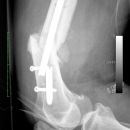

Fraktur Osteosynthese

Femurschaftfraktur